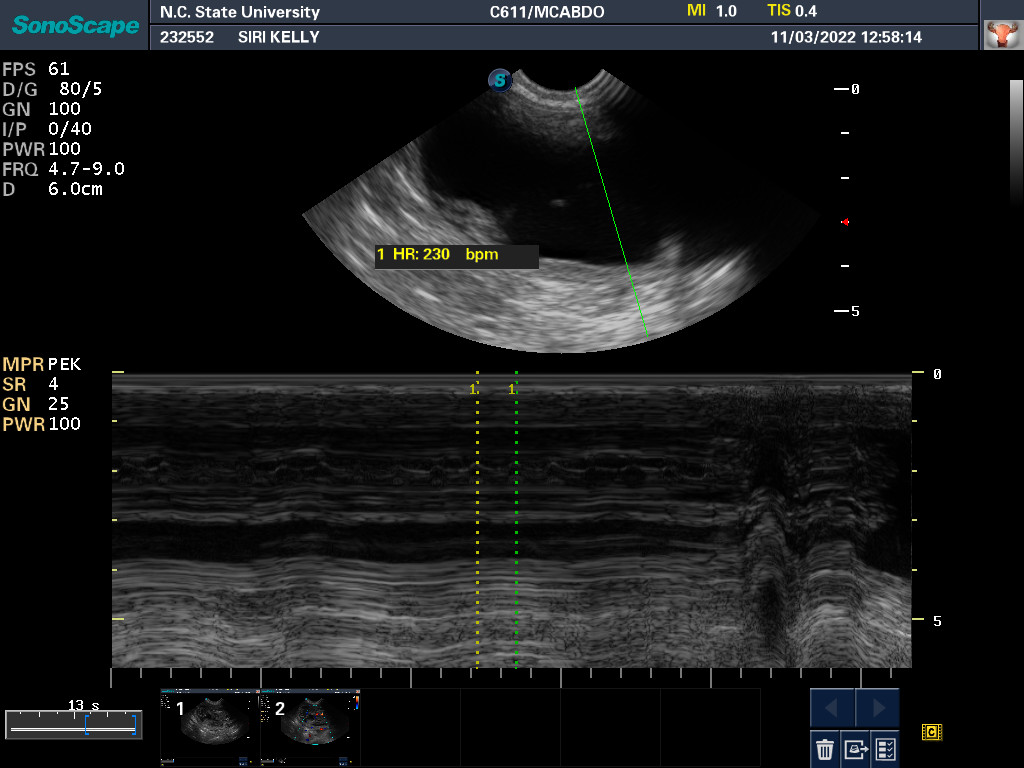

3 Nov 2022

Ultrasound today by the theriogenology (reproduction) veterinarians at NC State University showed that Siri is pregnant with possibly two puppies. It is difficult to accurately count puppies using ultrasound.

If all goes well, puppies are due around 28 November.